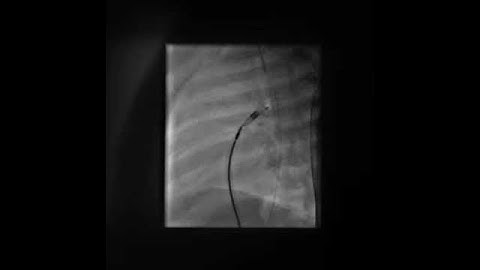

PDA Coil Closure Tiny PDA profiled